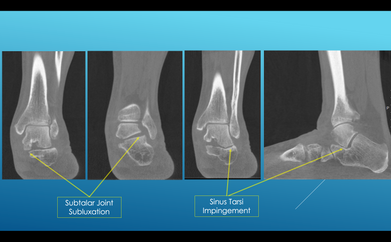

Flatfoot Deformity and Weight-Bearing CT: What is New?

In this FOOTinnovate webinar, Dr Cesar de Cesar Netto will go through recent publications and future perspectives on the advances of WBCT findings in the diagnosis and treatment of Flatfoot deformity.